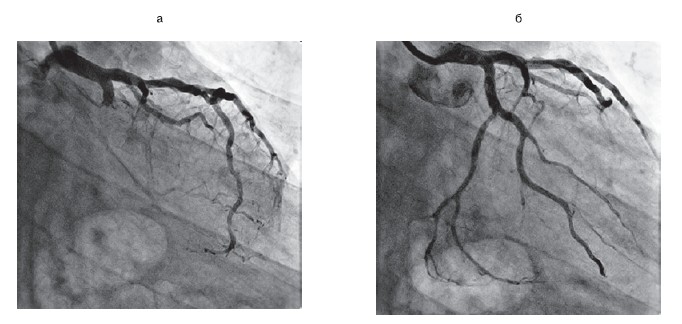

Рисунок 3.Пациент М., 63 года. Диагноз: Q-позитивный переднеперегородочный ИМ.

а — окклюзия ствола ЛКА; б — дистальное русло передней нисходящей и огибающей артерий слабо заполняется по коллатералям из правой коронарной артерии; в — остаточные стенозы после баллонной предилатации места окклюзии; г — «kissing» дилатация бифуркации ствола ЛКА после имплантации стентов; д, е — конечный результат после ЧТКА ствола и передней нисходящей артерии. ИМ — инфаркт миокарда; ЛКА — левая коронарная артерия.